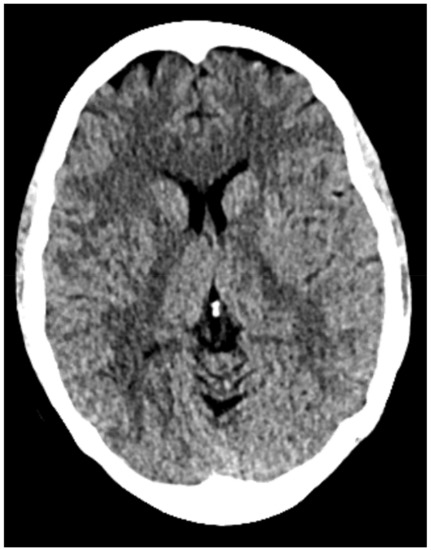

At our institution, four patients (n = 4) were assigned to acetazolamide therapy after they developed iatrogenic cerebrospinal fluid leak from transsphenoidal surgery for tumor resection from June 2018 to June 2019 by the senior neurosurgeon. Table 1 shows a summary of patient demographics. Average age was 42.5 years and average BMI was 31.6 (range 26.5–36.4). All four tumors were greater than 10 millimeters in size and had suprasellar extension (Hardy 3); in three of the four cases, the tumor compressed the optic chiasm and infiltrated the sphenoid sinus (Hardy 4). Further, in all four cases, the macroadenoma extended to or beyond the lateral aspects of the internal carotid artery, and in some cases extended into the superior and inferior cavernous sinus (Figure 2) compartment (Grade 3B). Average tumor volume was 21.24 [3]. Using the CSF leak grading system described by Esposito et al., all four patients had grade one to two CSF leaks, intra-operatively [8]. These leaks were repaired with a combination of dehydrated amniotic membrane, acellular dermis, and free mucosal flap based on the intraoperative judgement of the senior otolaryngologist.

Figure 2. Sagittal and coronal T1 contrast-enhanced weighted magnetic resonance imaging (MRI) demonstrating large sellar and suprasellar pituitary macroadenoma extending into the cavernous sinus.